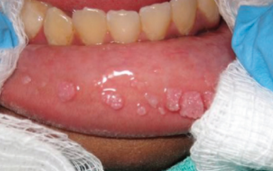

Oral Lesions

Alexander K.C. Leung, MD, MBBS, FRCPC, FRCP; Stamatia Alexiou, MD; Gary Griffin, MD; Brett Laggan, DDS; James J. Burns, MD, MPH

A 10-year-old African American boy with lumps in the mouth for the past 2 years. The lesions had increased in size and number.